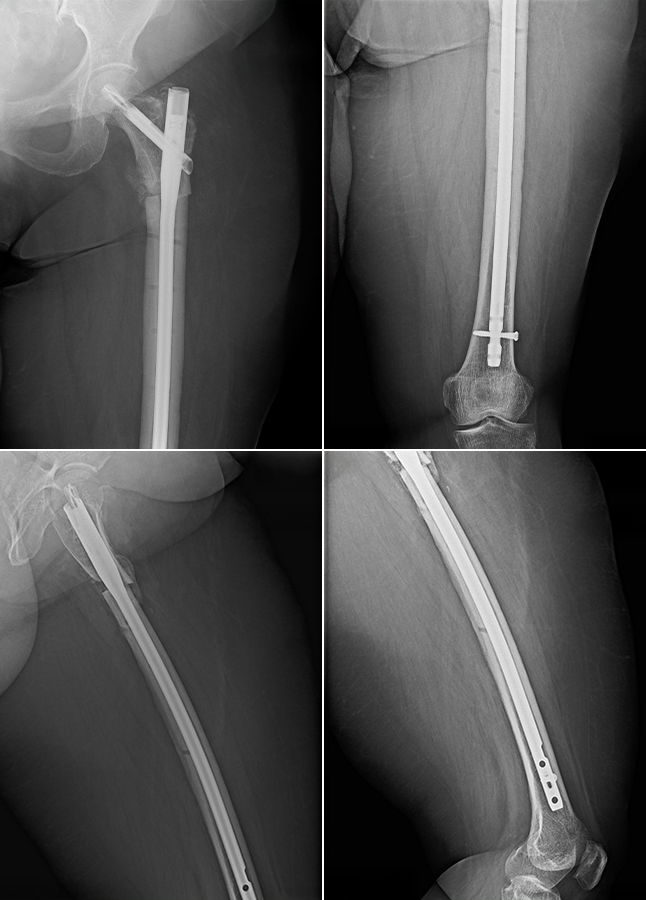

În urma accidentului, pacienta a suferit o fractură de femur proximal, pentru care s-a efectuat inițial o intervenție chirurgicală de osteosinteză prin reducerea fracturii și fixarea acesteia cu o placă metalică de tip DCS (Dynamic Condylar Screw). Alegerea acestui implant a fost influențată de particularitățile cazului, în special obezitatea de gradul III, care a limitat utilizarea unei tije centromedulare la momentul intervenției inițiale.

Placa DCS este un implant conceput în principal pentru fracturile femurului distal. Deși poate fi adaptată și pentru alte localizări, utilizarea sa la nivelul femurului proximal nu oferă întotdeauna o soluție biomecanică optimă, întrucât forțele exercitate în această zonă sunt considerabil mai mari. Aceste solicitări cresc riscul de suprasolicitare mecanică a implantului și pot întârzia sau împiedica procesul de consolidare osoasă.

La prezentarea în cadrul Spitalului Multidisciplinar Arcadia, pacienta acuza dureri importante la nivelul coapsei stângi, atât în repaus, cât și la mobilizare, asociate cu imposibilitatea sprijinului pe membrul inferior afectat. Examinarea imagistică (vezi imaginea aici) a evidențiat ruperea plăcii metalice și lipsa vindecării fracturii, cu apariția unei pseudartroze, o complicație în care capetele osoase nu se mai unesc, iar în zona fracturii se formează o articulație falsă ce împiedică consolidarea normală a osului.

În anamneză s-a remarcat și administrarea unui tratament medicamentos din clasa bisfosfonaților, utilizați pentru reducerea resorbției osoase. Deși aceste medicamente cresc densitatea osoasă, ele pot încetini procesul fiziologic de remodelare a osului, favorizând acumularea de microleziuni și crescând riscul de eșec mecanic al implanturilor, în special în condițiile unei încărcări mecanice crescute. Greutatea pacientei era similară cu cea de la momentul primei intervenții.